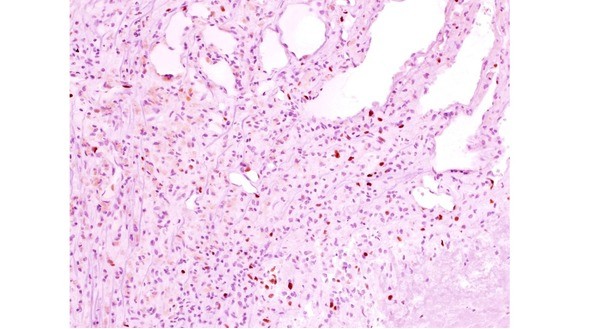

В последние годы проводятся иммуногистохимические исследования кавернозных мальформаций и окружающего мозгового вещества. Эти работы направлены на расшифровку механизмов формирования мальформации и ее биологического поведения (см. раздел «Этиология и патогенез). В исследованиях, выполненных в институте, при стандартном иммуногистохимическом исследовании КМ выявлена экспрессия мезенхимальных маркеров: виментина (Vim), гладкомышечного актина, и эндотелиальных маркеров CD31 и CD34 в стенках полостей мальформации (рис. 17 А, Б, В).

Экспрессия десмина (Des) в исследованных нами образцах отсутствует, пролиферативный индекс Ki-67 крайне низкий, исключая очаги капиллярной пролиферации и капсулы прилежащей гематомы (рис. 18).

Экспрессия фактора роста эндотелия сосудов VEGF, являющегося гликопротеином, влияющим на процессы ангиогенеза (рис. 19), а также эндоглина (СD105) и других факторов, участвующих в неоангиогенезе и сосудистой пролиферации, выявляется далеко не во всех кавернозных мальформациях.

Рис. 17. Иммуногистохимическое исследование кавернозных мальформаций. А. Экспрессия гладкомышечного актина (HHF 35) в стенках сосудистых полостей КМ (коричневое рашивание). ув. х 400. Б. Экспрессия эндотелиального маркера CD31 в эндотелии и тромбах, облитерирурющих сосудистые полости (коричневое окрашивание) Ув. х 200. В. Экспрессия эндотелиального маркера CD34 в эндотелии, выстилающем сосудистые полости (коричневое окрашивание). Ув. х 400

Рис. 18. Экспрессия пролиферативного маркера Ki-67 в КМ (коричневое ядерное окрашивание, индекс 5%) в формирующейся капсуле гематомы. Ув. х 200

Рис. 19. Экспрессия VEGF в формирующемся тромбе (1) и в эндотелии (2) сосудистой полости КМ (коричневое окрашивание). Ув. х 400